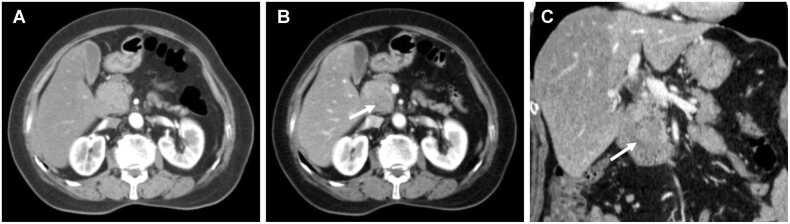

A total of 149 patients were evaluated (median age: 67 years; interquartile range: 41-89 years; 82 men), among whom 70 (47.0 %) experienced early recurrence. Rim enhancement, tumor necrosis, peripancreatic tumor infiltration, and suspicious metastatic lymph nodes, were independently associated with early recurrence. When any two or more of these four significant imaging features were combined, the specificity was 86.1 % (68/79) and the sensitivity was 88.6 % (60/70). DFS and OS were significantly worse in PDAC patients with two or more of these features compared to those with none or only one (all log-rank  < 0.001).

A combination of two or more imaging features such as rim enhancement, tumor necrosis, peripancreatic tumor infiltration, and suspicious metastatic lymph nodes, could be used as a prognostic imaging marker for early recurrence, demonstrating effective diagnostic performance and an association with DFS and OS after pancreatoduodenectomy of PDAC.